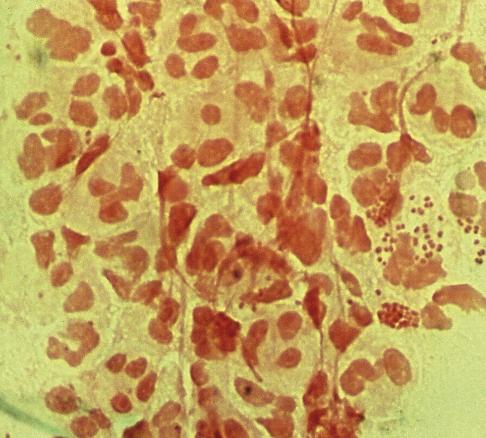

Un homme de 30 ans consulte pour une douleur ano-rectale intense évoluant depuis 24 heures avec des faux besoins glairo-sanglants. Il prend une prophylaxie pré-exposition contre le VIH. La marge anale est normale. L’anuscopie montre une rectite érythémateuse avec des sécrétions purulentes (fig. 1 ).

Le diagnostic est évoqué sur l’anamnèse et la clinique. Il est confirmé par l’analyse polymerase chain-reaction (PCR) d’un écouvillonnage rectal détectant simultanément Neisseria gonorrhoeae (fig. 2 ) et Chlamydia trachomatis. Ce prélèvement permet également la réalisation d’un antibiogramme.